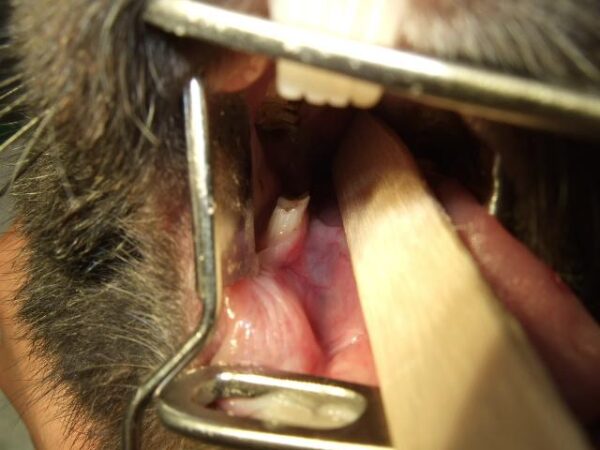

- 重度の場合:伸びた歯が舌や頬に刺さり、傷ができ(写真①)、痛みから元気や食欲がなくなり、体重が減少することもあります。

歯の処置には麻酔が必要となるため、当院ではまず血液検査やレントゲン検査を行い、安全に麻酔をかけられるかを慎重に確認します。安全が確認できた上で麻酔をかけ、臼歯の噛み合わせ(咬合)を考慮しながら歯を削る処置を行います(写真②、写真③)。術後は、点滴や腸の動きを促進する薬、鎮痛剤を投与し、速やかな回復をサポートします。